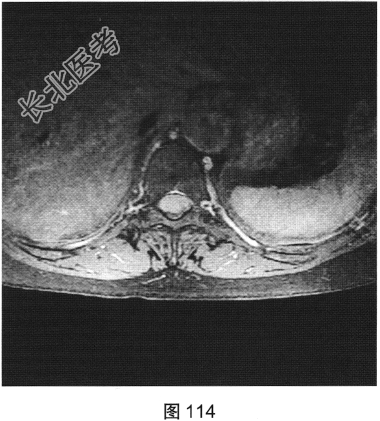

- [材料题] 患者女性,59岁,无明显诱因出现腰背部疼痛伴双下肢麻木1年,久行、久坐、久站或咳嗽、排便时疼痛加重,休息后症状缓解,1个月前腰背部麻木疼痛突发加重,行走100米既感疼痛难忍,伴双下肢无力疼痛。查体:脊柱无明显侧弯,相当于T₁₀平面以下感觉减退,腰椎活动度受限,无紧张,棘突旁压痛、叩痛,向双下肢放射。挺腹试验阳性,跟臀试验(+),双侧直腿抬高试验(一),双下肢小腿外侧、足背感觉稍差,双侧

背伸肌肌力4级;肌张力正常,双侧巴宾斯基征可疑阳性。实验室检查:人类白细胞抗原B27阴性(一),RF<10U/ml(正常值0~15U/ml)。

- 简答题2、患者行MRI检查,如图111~图114所示。根据患者病史及影像学检查,请问其最可能的诊断是什么?

- 简答题3、请对脊膜瘤进行描述。